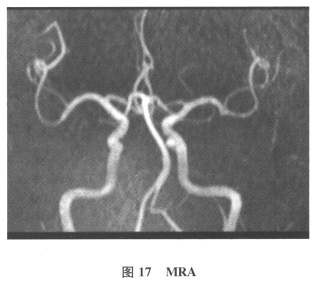

[多选题]患者男,61岁。因“发作性头晕2年,加重伴记忆力下降、走路不稳3月余”就诊。查体:BP140/70mmHg;意识清楚,构音障碍,近期记忆力及远期记忆力